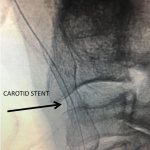

Figure 1.

This 77-year-old man with a history of stroke in 2013 presented to a small community hospital with aphasia upon awakening. Given the unclear timing of onset of his symptoms he was not deemed a candidate for intravenous thrombolytic. His NIHSS was 2 in the emergency room. He was admitted to the hospital where a CT (Figure 1) and CTA were performed showing a left frontal small infarct and severe extracranial carotid stenosis on the left. MRI could not be performed because of the patient’s pacemaker. Examination was significant for an awake gentleman with normal cranial nerve function and normal motor exam but significant expressive aphasia. Receptive aphasia was intact. He was placed on Aspirin.